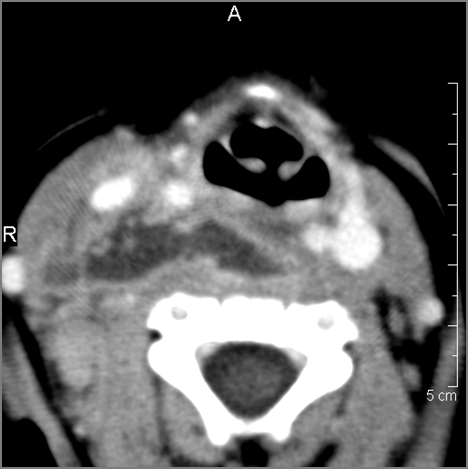

Cervical Lymph Nodes

If there is suppurative cervical adenopathy the purulent material outside the lymph node(s) capsule(s).